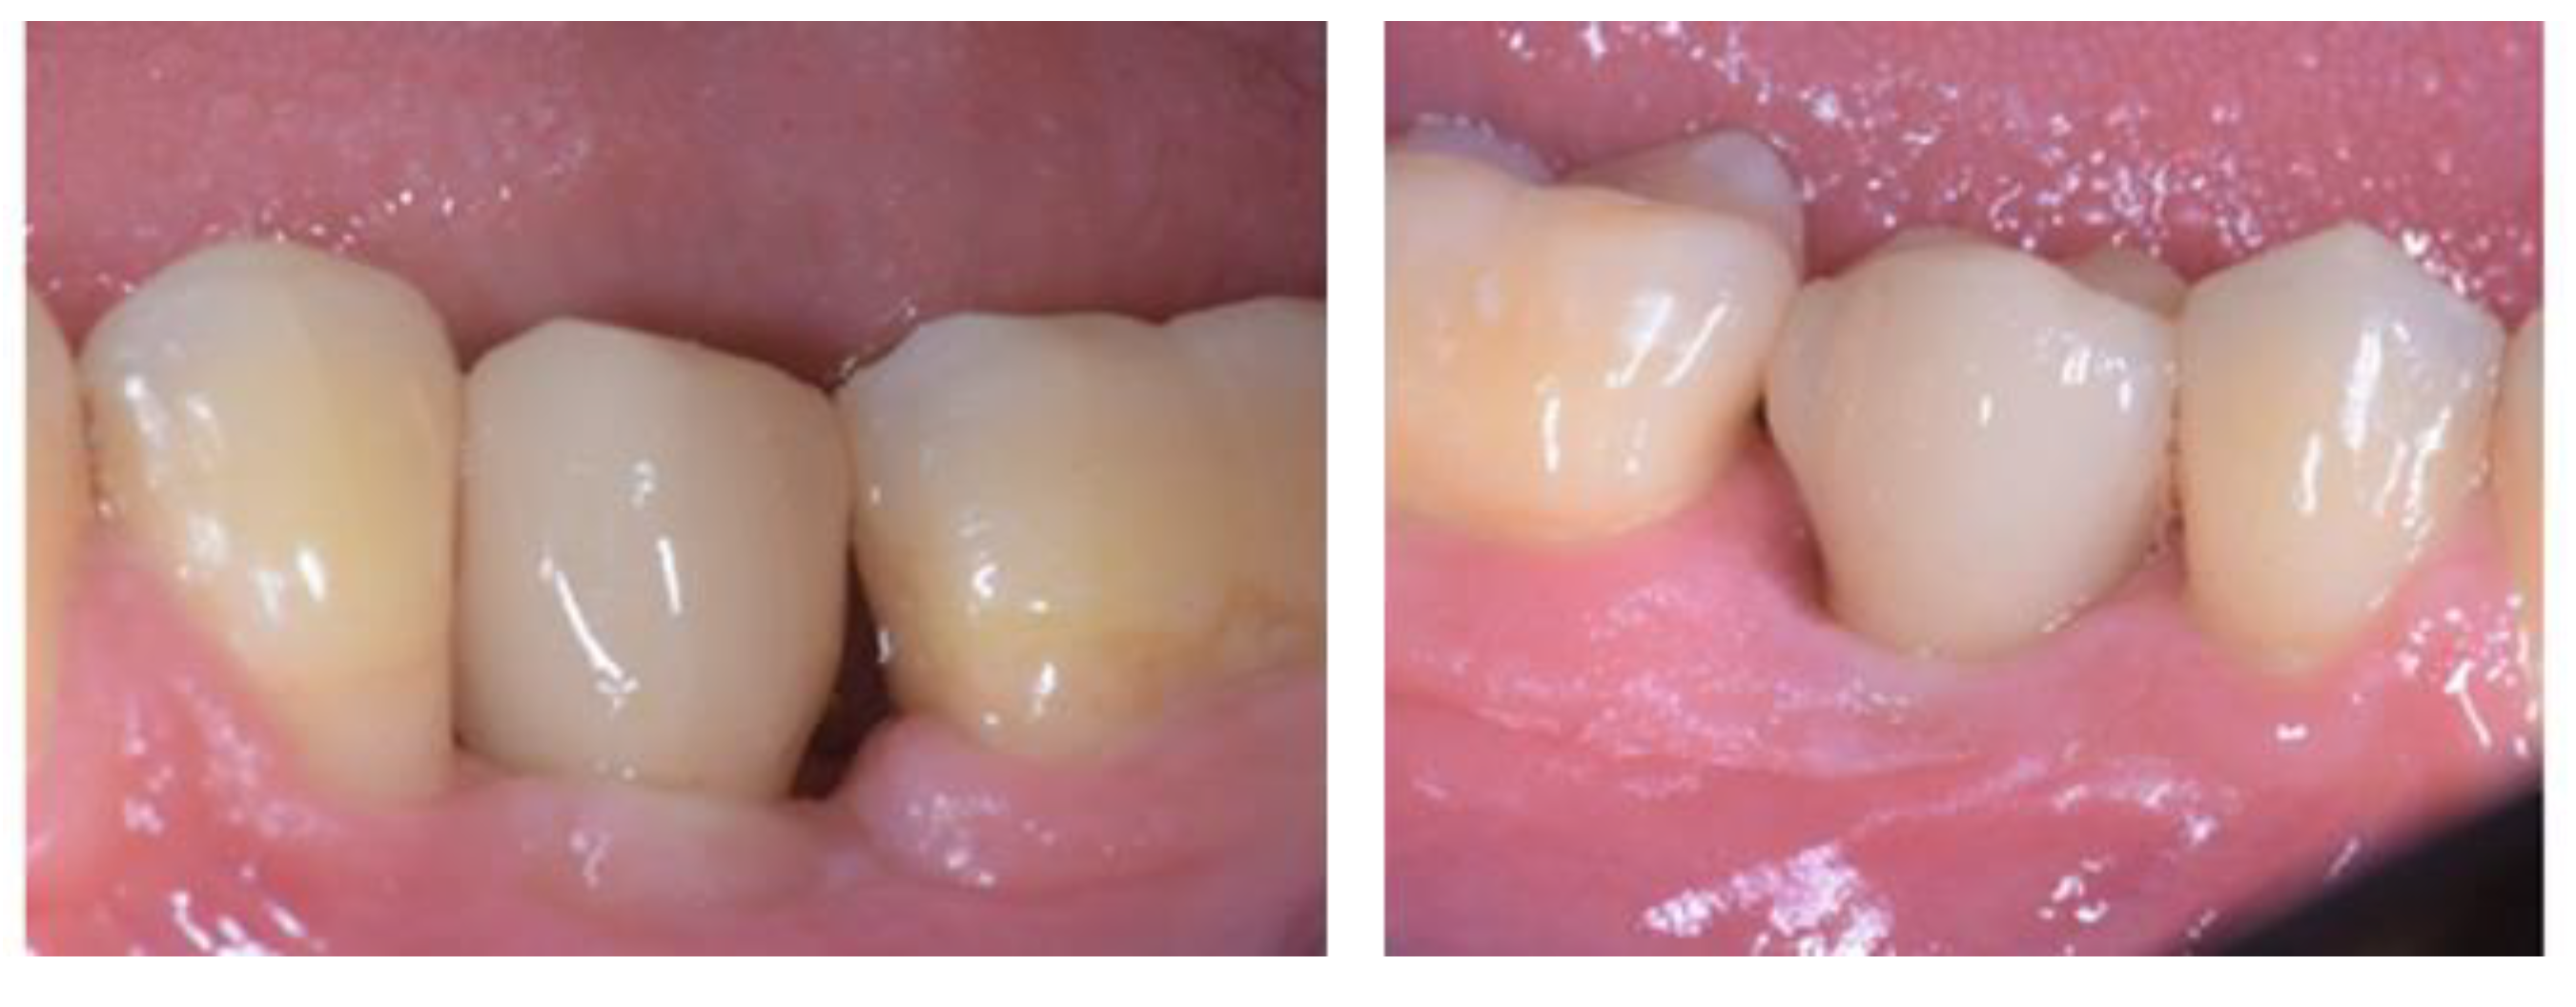

- Case 1:

- Case 2:

- Case 3:

- Case 4:

- Case 5: